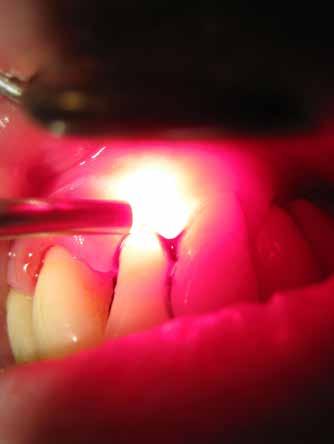

sok korrigálása, valamint az impaktálódott fog előtöréséhez szükséges hely megteremtését követően, egy merev acél ív segítségével stabilizáltuk a fogakat. Ezt követően elvégeztük a jobb felső nagymetszőfog sebészi feltárását. A fog koronáját csupán lágyrész borította, ezért nem volt szükség a csontállomány elvételére. A felszabadítás során egy 975

nm-es hullámhosszon pulzáló üzemmódban alkalmazott lézert használtunk (LaserHF standard, Hager & Werken). A teljesítménye 3 W, az aktív ciklus-idő 50%-os, a vezetőszál átmérője pedig 0,4 mm volt (2. ábra). A lézert 150 másodpercen keresztül alkalmaztuk. A fogat borító lágyrészek eltávolítását követően egy láncos brekettet rögzítettünk a metszőfog bukkális felszínére. A műtétet követően nem tapasztaltunk vérzést, nem alakult ki oedema, valamint a páciens sem számolt be fájdalom vagy bármely egyéb kellemetlenség fennállásáról. A felszabadítást követően a páciens minden hónapban háromszor jelent meg a felszabadított területre ránövő lágyrészek és az íny lézeres eltávolítása céljából. A beavatkozások során ugyanazt a lézer készüléket használtuk, mint amivel a felszabadítást végeztük. Közvetlenül a felszabadítást követően megkezdtük a fog finom extrudálását a láncos breketthez kötött füzérgumi segítségével.